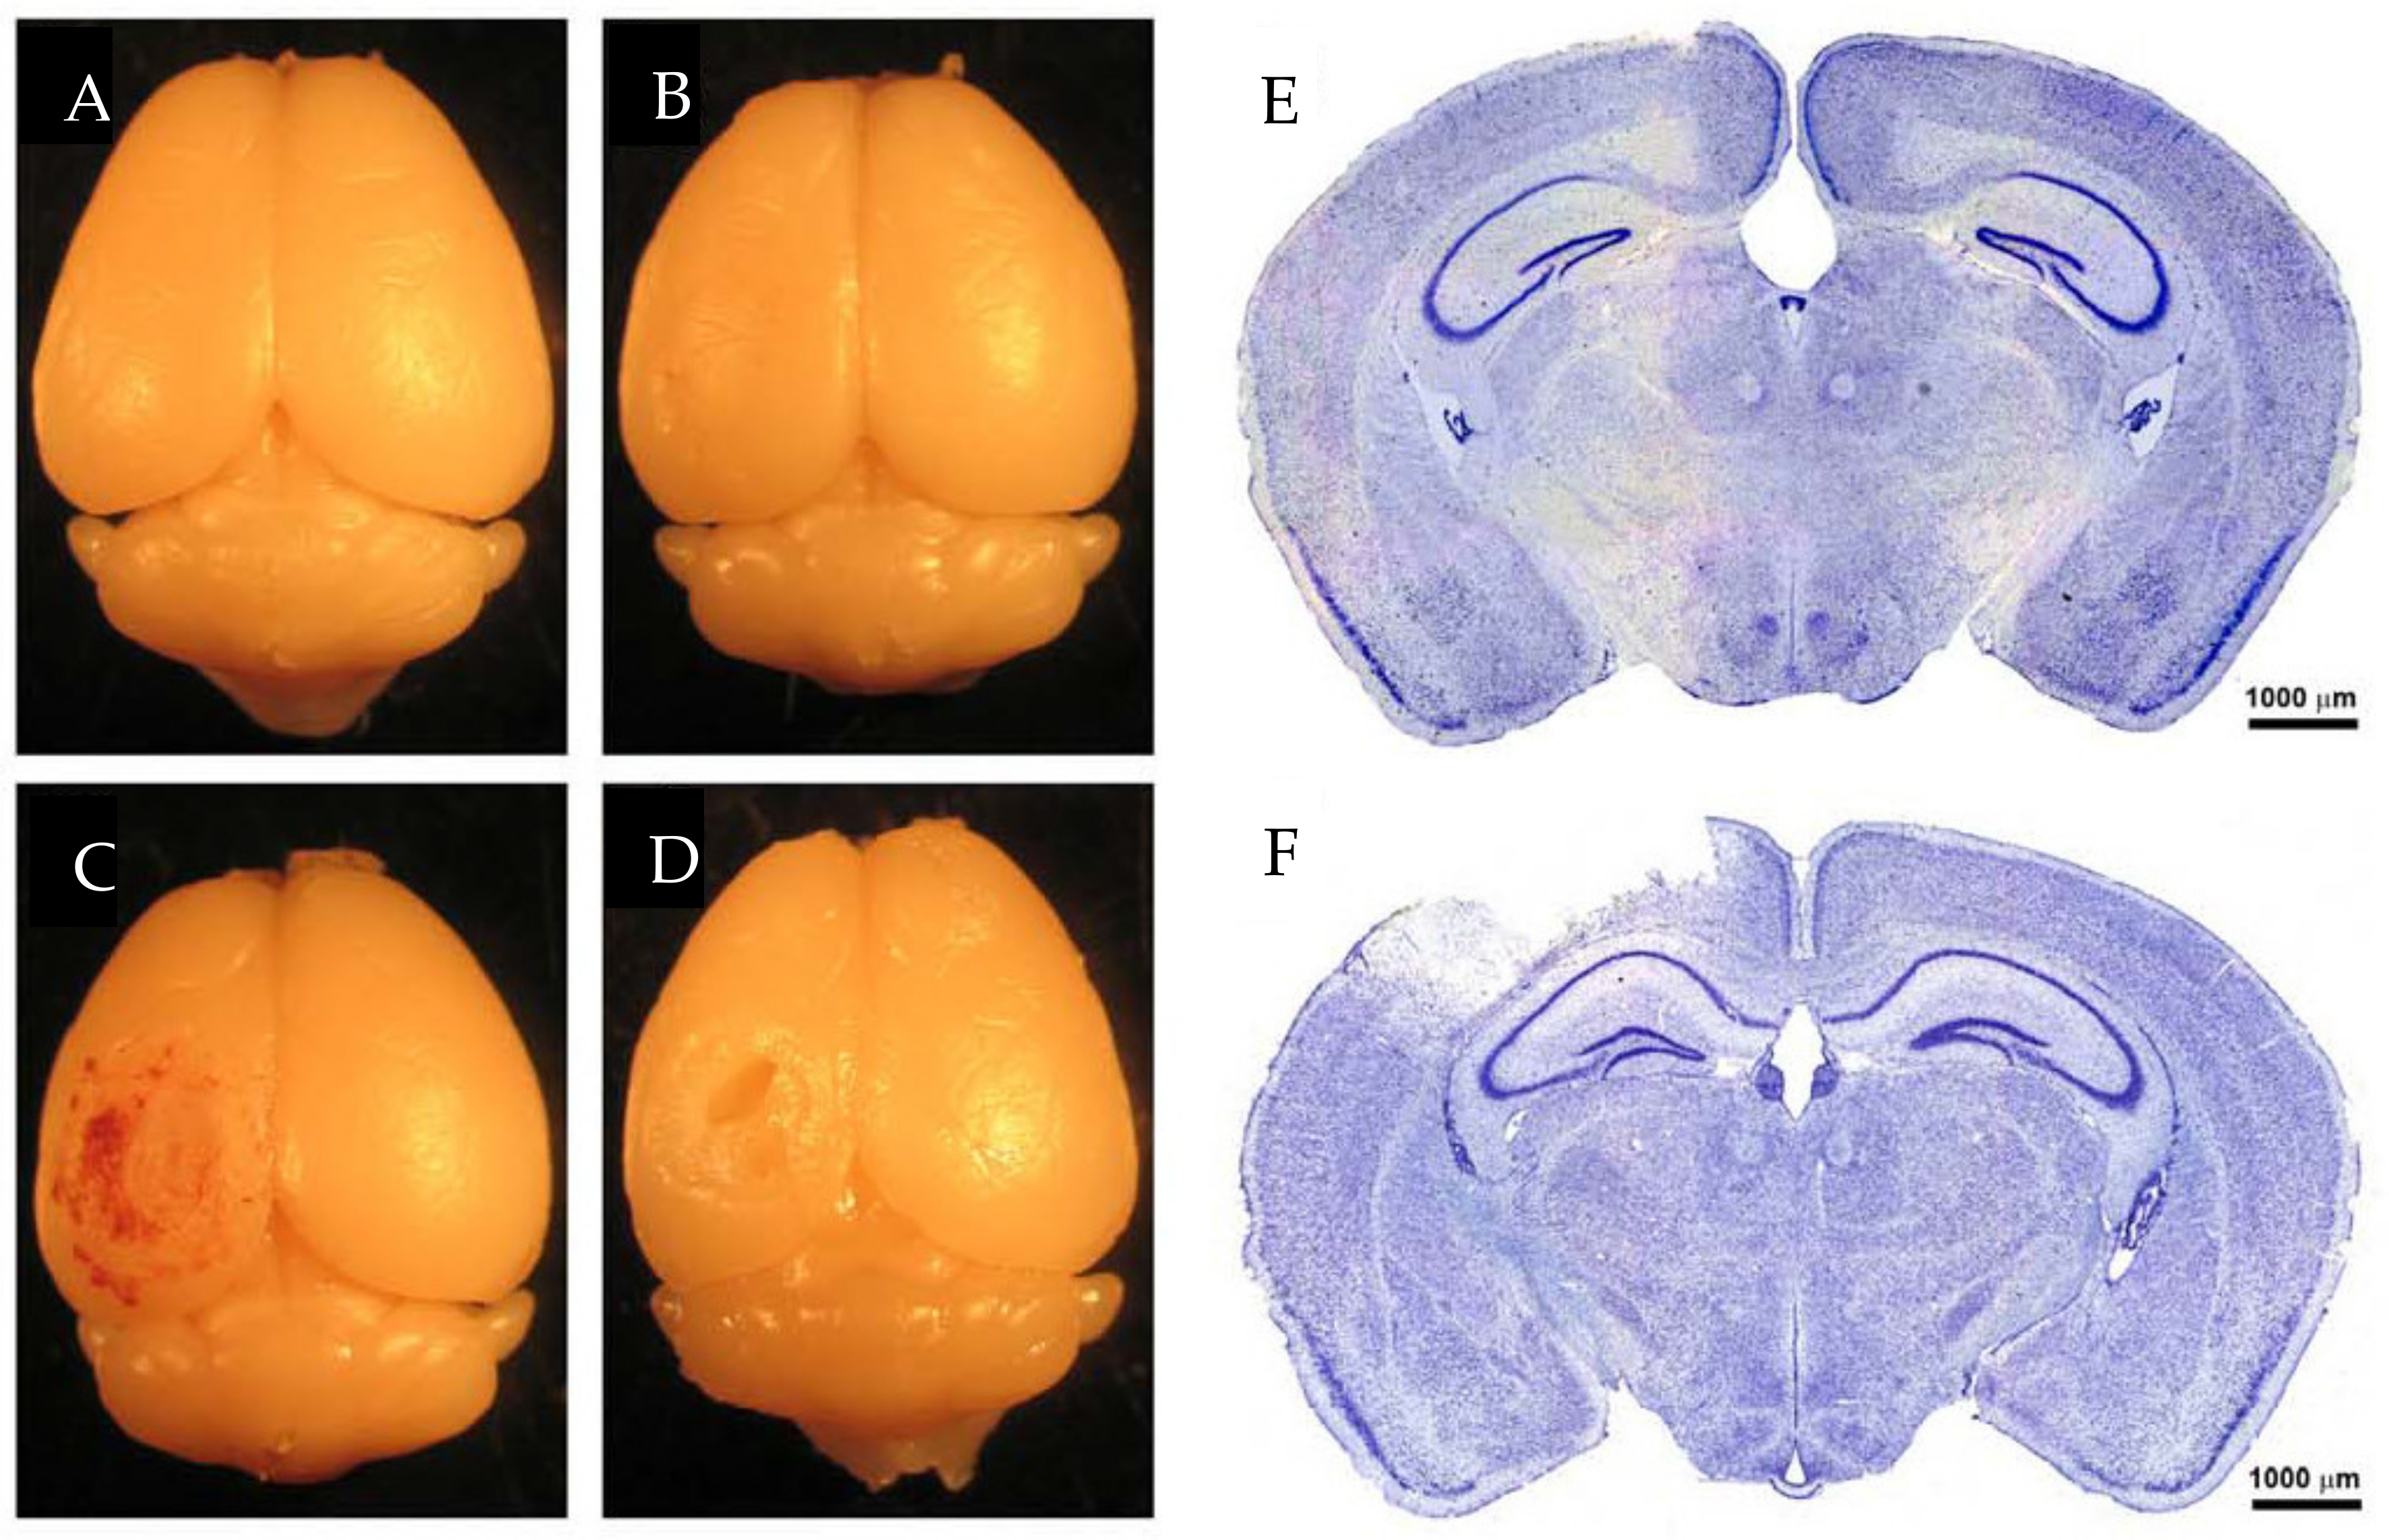

6. Diffuse TBI

6.1. Marmarou Weight Drop Model

6.2. Modified Marmarou Weight Drop Model

6.3. Modified Controlled Cortical Impact

6.4. Repeated Mild TBI

7. Non-Impact TBI

7.1. Closed-Head Impact Model of Engineered Rotational Acceleration (CHIMERA)

7.2. Blast Injury Model